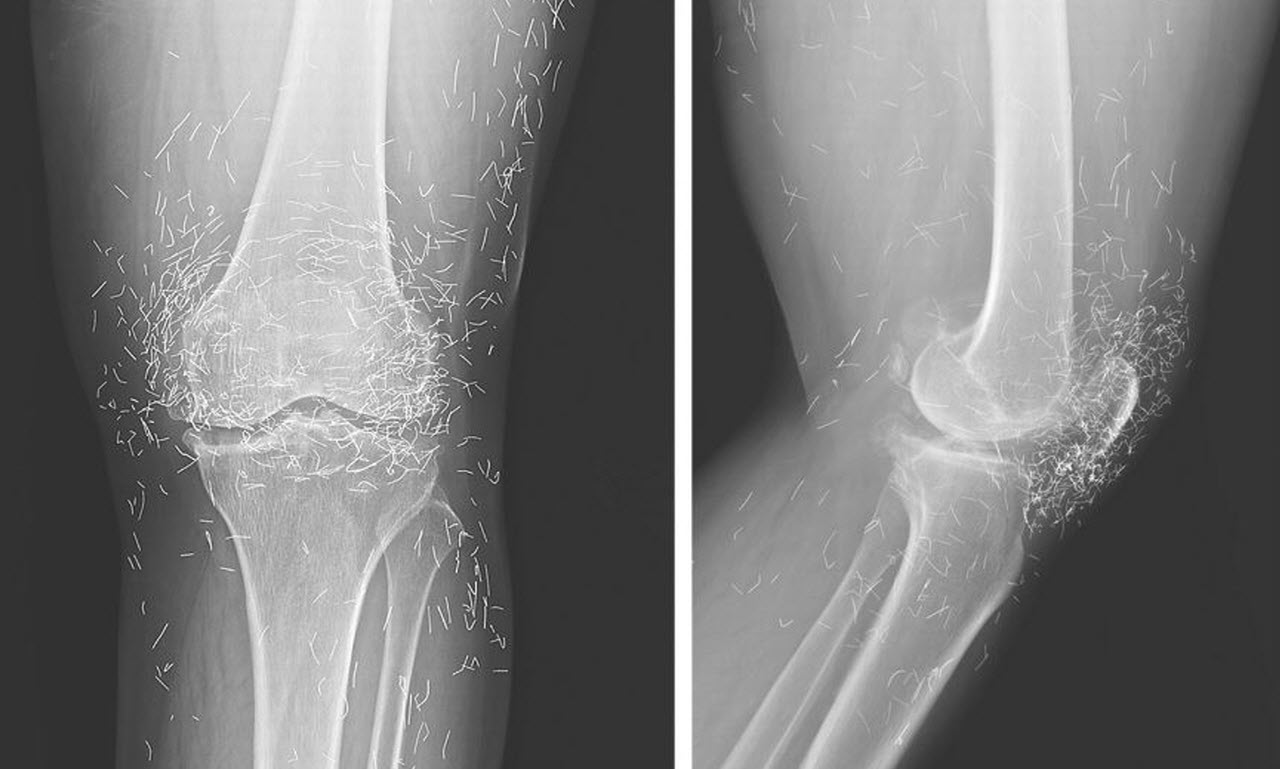

A 65-year-old woman from South Korea went to doctors for severe joint pain, and her X-ray ended up showing something very strange. The scan revealed hundreds of small gold needles left inside her knee tissue, and it stunned the medical team who looked at it.

Acupuncture uses thin needles placed in certain points on the body to ease pain. In her case the doctors said the gold needles were left inside on purpose, the idea being to give constant stimulation to the painful area.

There are more dangers too. If needles stay in the tissue they can block medical scans. The doctor also said: “They can obscure parts of the anatomy on an X ray.” He added that if a patient with metal fragments ever has an MRI, the magnets could make the pieces move and maybe even cut blood vessels.